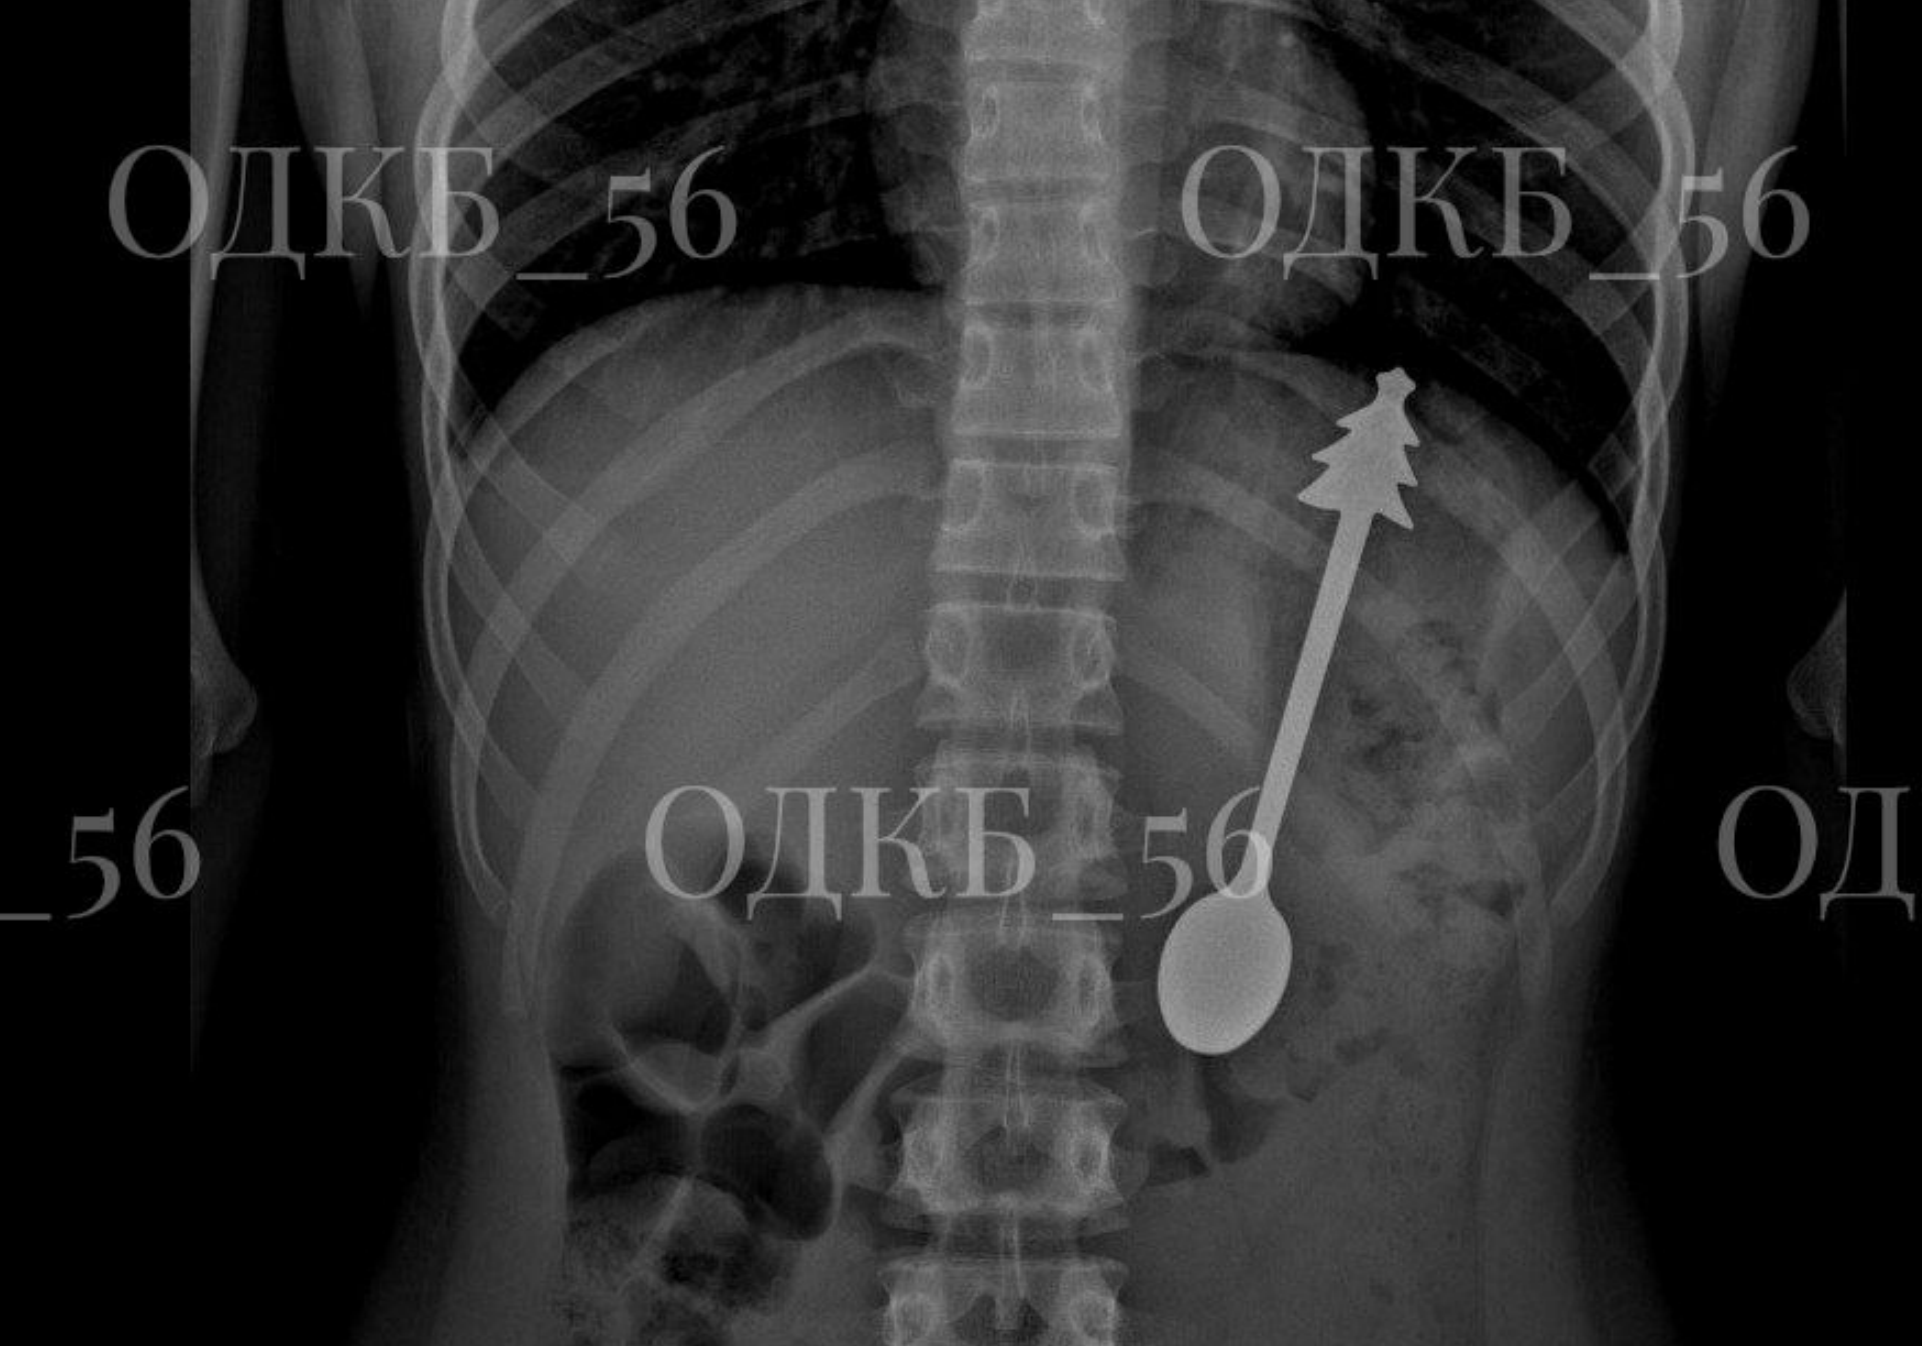

В Оренбурге врачи детской областной больницы провели уникальную операцию, спасая ребёнка, проглотившего ложку. Маленького пациента доставили на «скорой» в экстренном порядке, и рентген показал в желудке крупный металлический предмет.

Специалисты первого детского хирургического отделения немедленно провели сложную эндоскопическую операцию под общим наркозом. В ходе вмешательства из организма ребёнка извлекли целую металлическую ложку длиной 14 сантиметров. Процедура прошла успешно, без осложнений, и уже на следующий день малыша выписали домой в удовлетворительном состоянии.